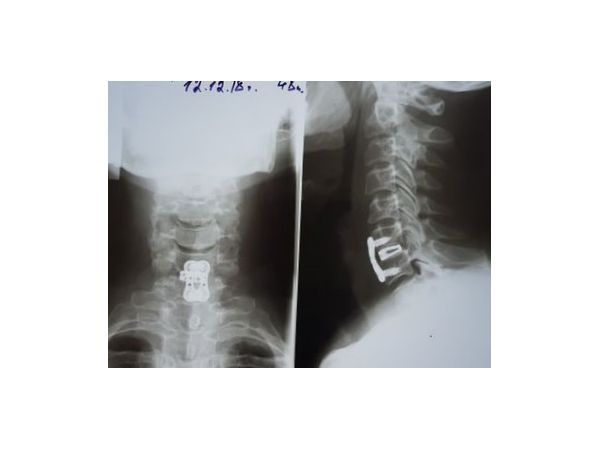

Операция выполнена 11.12.2018. Она длилась 2 часа 15 минут и включала в себя:

• передний межтеловой спондилодез (соединение позвонков) вентральным межтеловым шейный кейджем и односегментарной шейной пластиной с четырьмя блокирующими винтами.

4. В межтеловое пространство установлен аутотрансплантат. Произведена фиксация титановой пластиной на четырёх винтах. Выполнен контроль установки трансплантатов и пластинки с помощью ЭОП — положение адекватное. Рана промыта водным раствором хлоргексидина и перекиси водорода. Наложены швы на платизму, подкожную фасцию, косметический шов на кожу и спиртовая повязка.

• блокирующие винты Double Medical 14 мм для фиксации шейной пластины — 4 шт;

• вентральный межтеловой шейный кейдж Double Medical — 6 мм;

• вентральная односегментарная шейная пластина Double Medical — 25 мм.